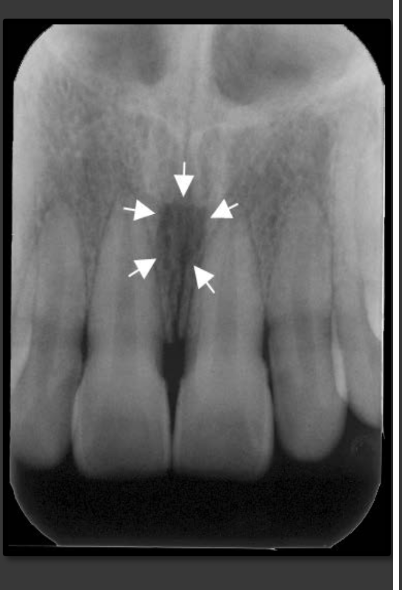

How does the incisive foramen present in a radiograph?

It is a radiolucency that presents between the roots of the maxillary centrals. It is variable in shape, size, and border.

How does the median palatine suture present in a radiograph?

A thin radiolucent line that runs directly between the maxillary incisors.